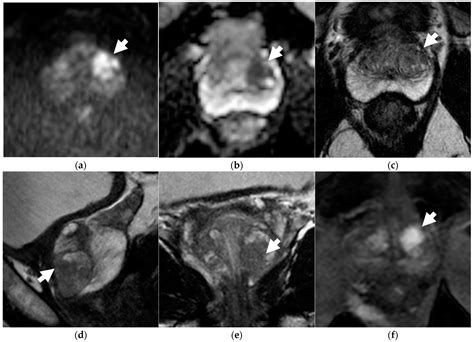

• T2-weighted imaging: Provides detailed anatomical images of the prostate.

• Diffusion-weighted imaging (DWI): Measures the movement of water molecules within tissues to detect areas of restricted diffusion, which may indicate cancer.

• Dynamic contrast-enhanced (DCE) MRI: Uses a contrast agent to assess blood flow and vascularity within the prostate, helping to identify areas of increased blood flow that may be associated with cancer.

• Functional MRI: Functional MRI techniques, such as diffusion-weighted imaging and dynamic contrast-enhanced MRI, provide additional information about the metabolic and vascular characteristics of prostate tumors. This can help to differentiate between benign and malignant lesions.